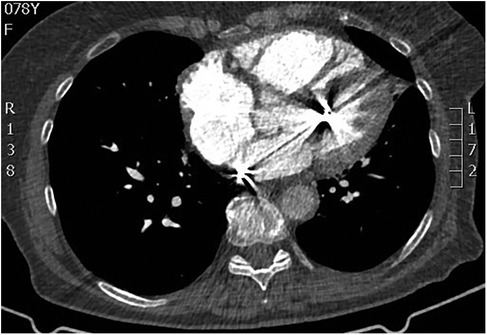

Transesophageal echocardiography (TEE) demonstrated a superior sinus venosus defect near the junction of the superior vena cava (SVC) and right atrium with left-to-right shunting. Two pacing leads pass through the defect from the SVC into the left side of the heart, with one lead affixed to the left atrium roof and the other extending through the mitral valve without any perforations into the left ventricle, where it is fixed to the interventricular septum. No intracardiac thrombi, or “smoke” and thrombi on pacemaker leads were observed during TEE (Figures 2, 3). A contrast-enhanced computer tomography (CT) scan of the chest was performed to further evaluate the suspected congenital defect and confirm the position of malpositioned pacing leads (Figure 4). CT imaging confirmed the presence of a superior sinus venosus defect located near the junction of the SVC and the right atrium. Moreover, CT revealed partial anomalous pulmonary venous return, with the right superior and middle pulmonary veins draining into the SVC. Given the patient's age, moderate frailty, and absence of significant clinical symptoms, a conservative approach was adopted. Lead extraction was not pursued due to high procedural risk. The patient was managed with lifelong oral anticoagulation with warfarin to mitigate the risk of systemic thromboembolism. Surgical correction of the anomalous pulmonary venous return was not indicated, as the patient remained hemodynamically stable without signs of volume overload. Ongoing follow-up includes regular assessment of anticoagulation status, pacemaker function, and clinical condition. The patient remained clinically stable during follow-up. No thromboembolic or bleeding complications were observed. TTE and x-ray demonstrated stable lead positioning within the left heart chambers, without evidence of thrombus formation or endocardial damage. Pacemaker function remained intact with appropriate sensing and pacing parameters.

Figure 4

CT scan demonstrating malpositioned cardiac pacing leads located within the left heart.